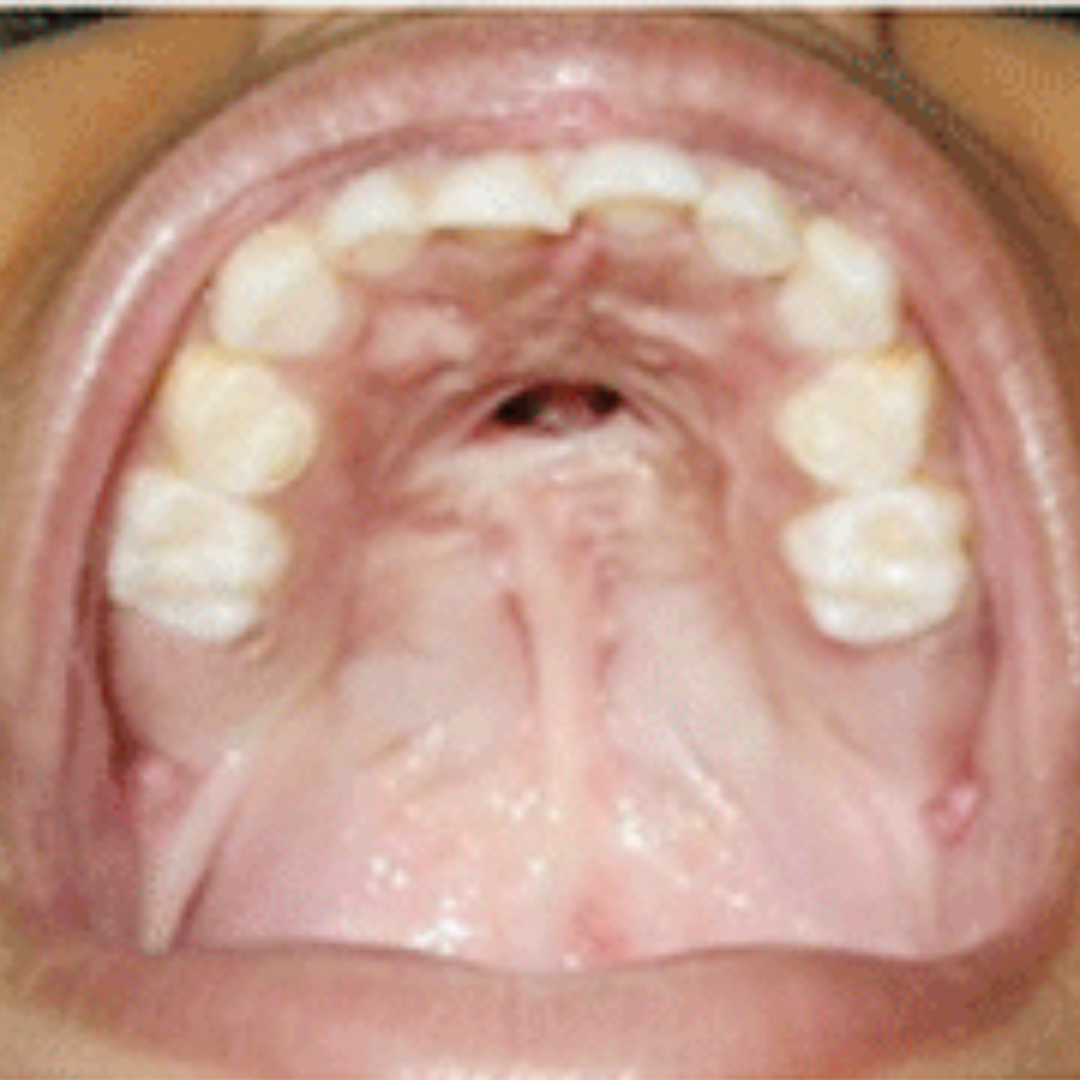

Fistula repair is a surgical procedure done to close an abnormal opening (called a fistula) that forms between the mouth and nasal cavity after cleft palate surgery. These fistulae are unintended holes that occur when the tissue doesn’t heal properly after the initial cleft repair. The goal of the repair is to restore proper function for speech, eating, and prevent nasal regurgitation.

- Visible hole or opening in the roof of the mouth

Clinical exam and imaging (MRI, CT, fistulogram) help assess the fistula’s type, size, and location. Speech function is also reviewed.